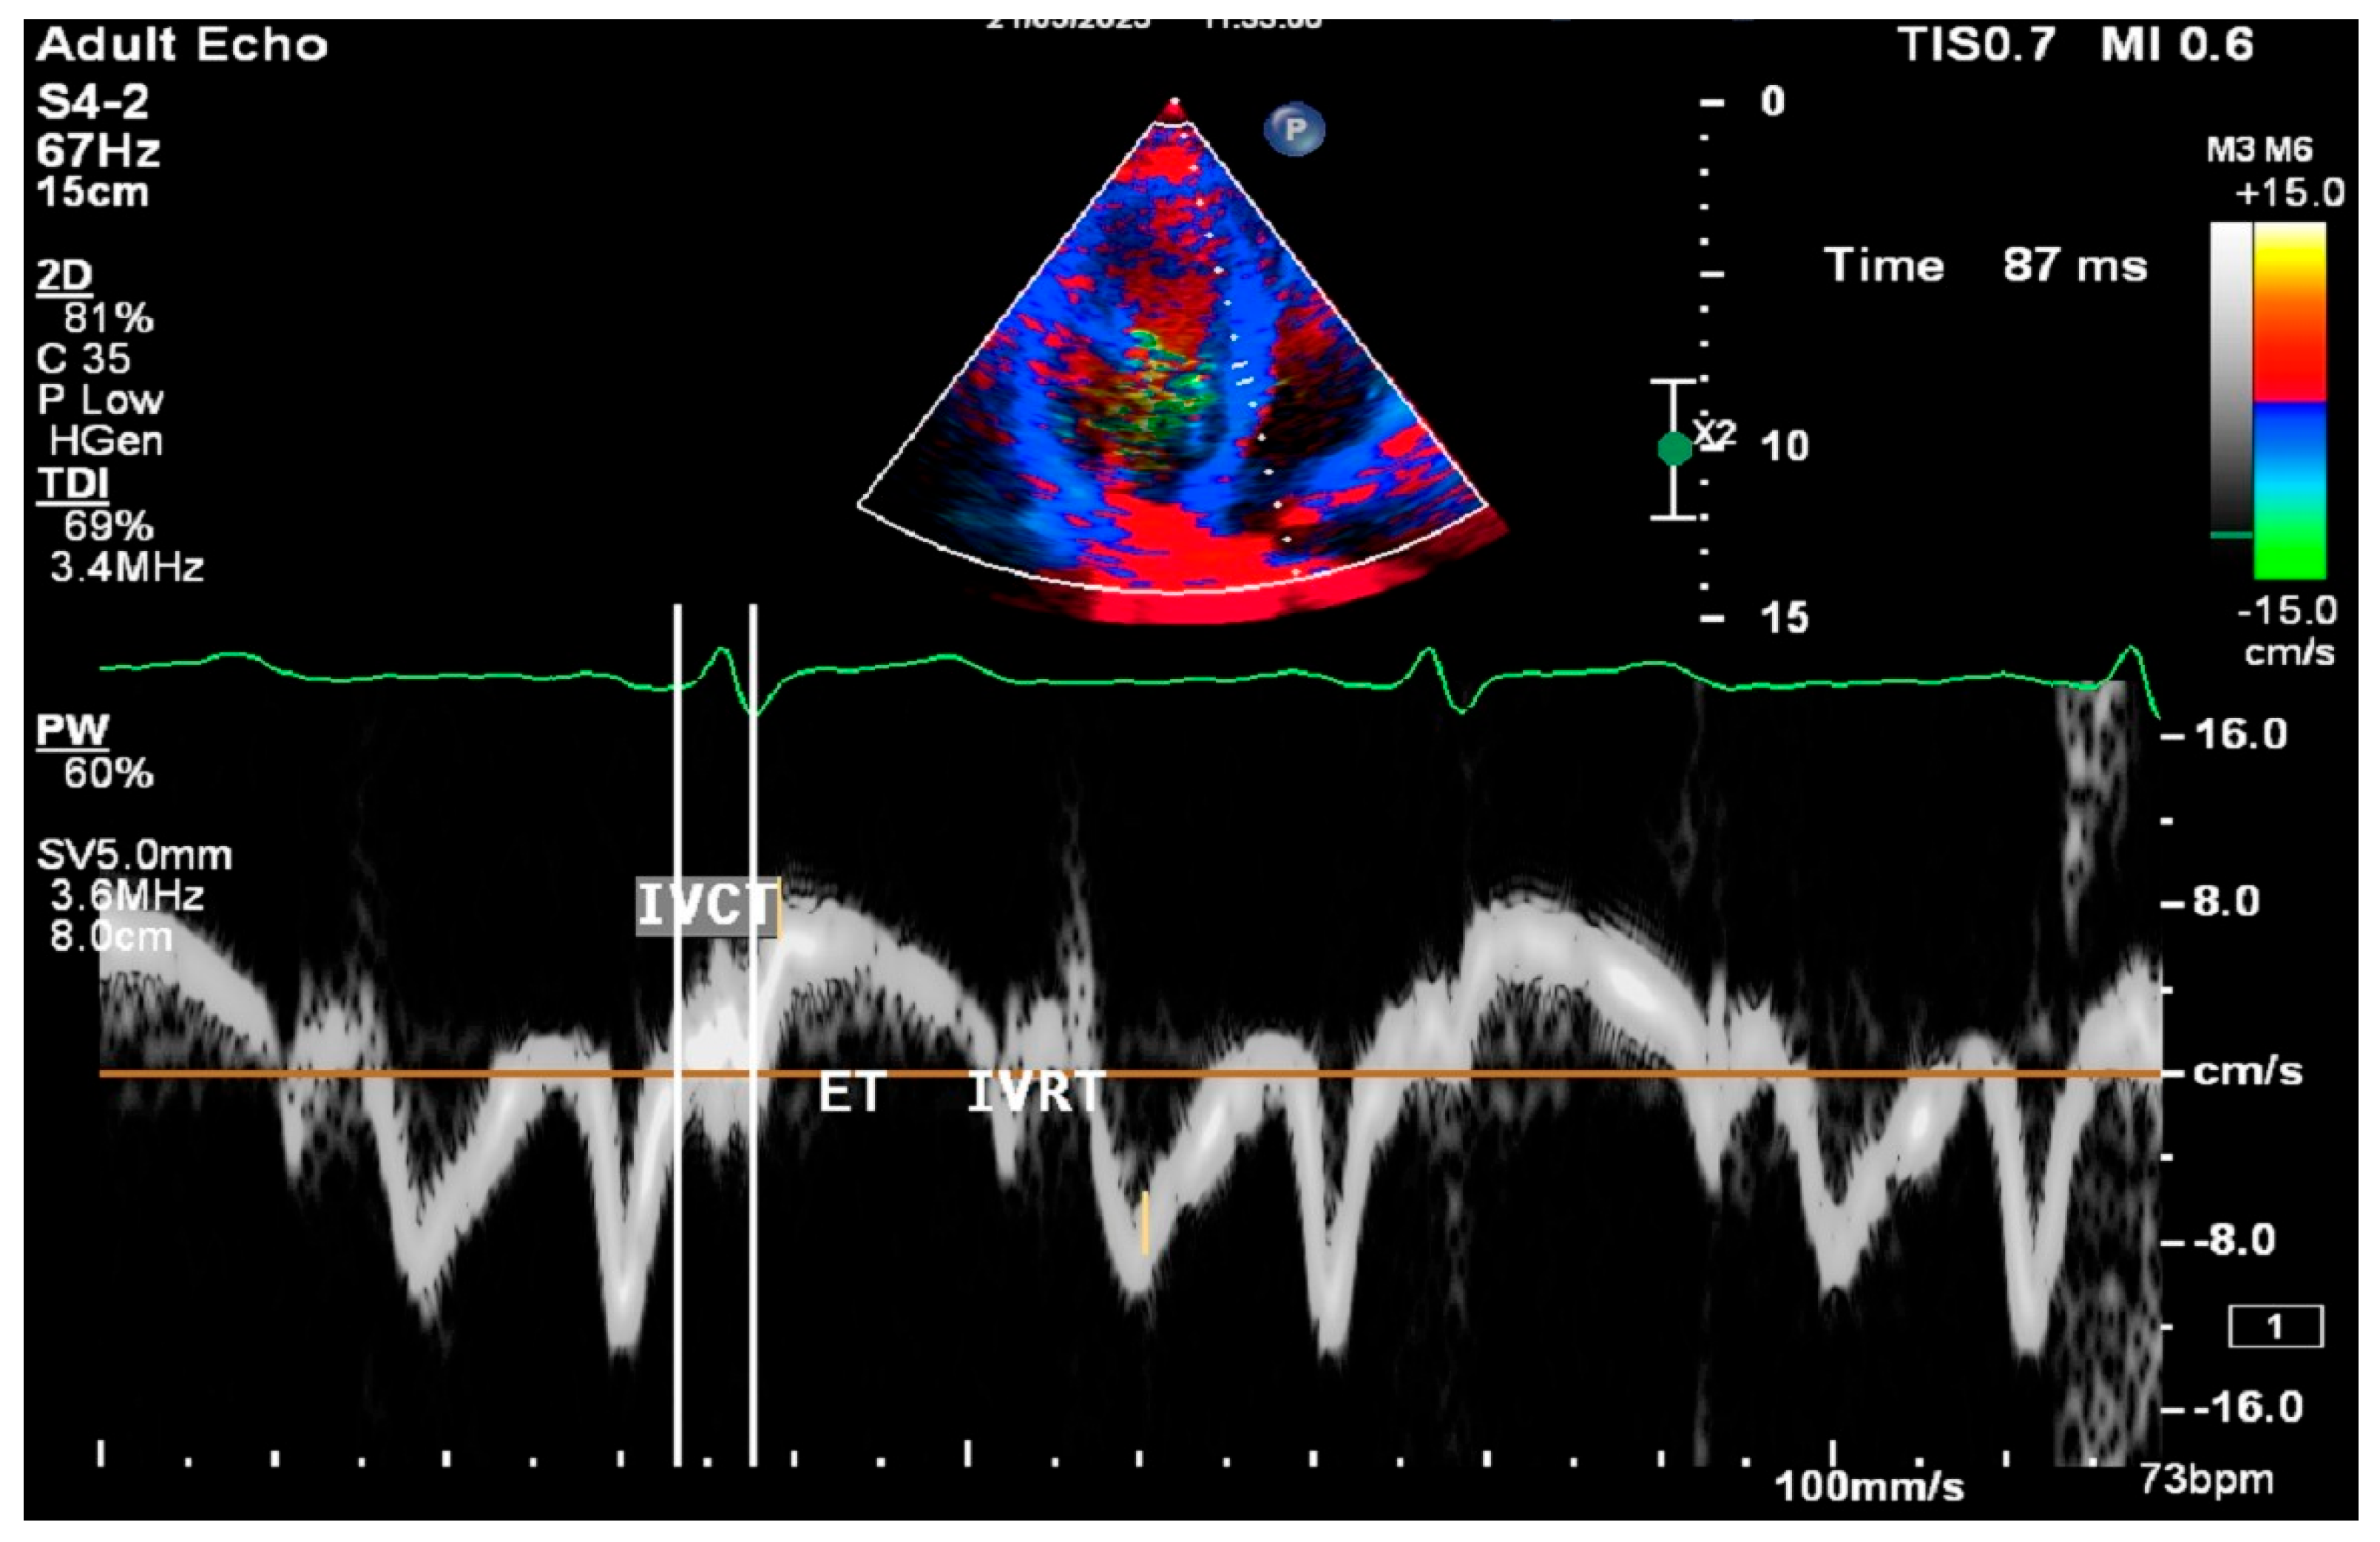

2.8. Cardiac Ultrasound Examinations